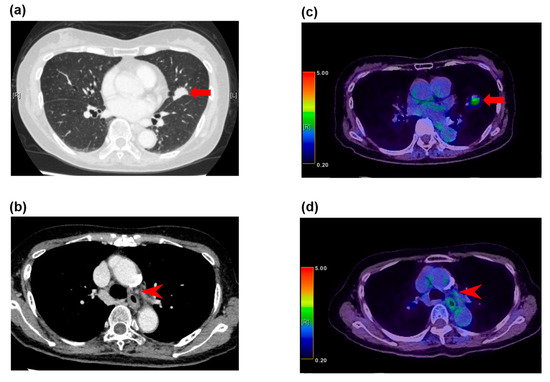

Figure 2.

False positive FDG-PET/CT findings in enlarged lymph nodes in a 78-year-old man with squamous cell carcinoma. (a) The CT image shows a left upper lobe tumor (arrow), (b) and enlarged station 5 lymph nodes (arrowhead). (c) The FDG-PET/CT image shows FDG accumulation with a maximum SUV of 6.9 (arrow) in the squamous cell carcinoma in the left upper lobe, (d) and FDG accumulation with a maximum SUV of 3.9 in the enlarged station 5 lymph nodes (arrowhead). These lymph nodes demonstrated granulomatous inflammation at histopathologic examination of the specimen from surgical biopsy.